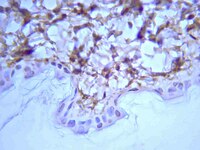

The study aimed to evaluate osteogenic properties of hydroxyapatite (HA) scaffold combined with extracellular matrix (ECM) derived in vitro from rat primary calvarial osteoblasts or dermal fibroblasts. The cellular viability, and the ECM deposited onto synthetic HA microparticles were assessed by MTT, Glycosaminoglycan, and Hydroxyproline assays as well as immunohistochemistry and scanning electron microscopy after 21 days of culture. The decellularized HA-ECM constructs were implanted in critical-sized calvarial defects of Sprague-Dawley rats, followed by bone repair and local inflammatory response assessments by histomorphometry and immunohistochemistry at 12 weeks postoperatively. We demonstrated that HA supported cellular adhesion, growth, and ECM production in vitro, and the HA-ECM constructs significantly enhanced calvarial bone repair (p<0.05, Mann-Whitney U-test), compared with HA alone, despite the significantly increased number of CD68+ macrophages, and foreign body giant cells (p<0.05, Mann-Whitney U-test). Selective accumulation of bone sialoprotein, osteopontin, and periostin was observed at the tissue-HA interfaces. In conclusion, in vitro-derived ECM mimics the native bone matrix, enhances the osteogenic properties of the HA microparticles, and might modulate the local inflammatory response in a bone repair-favorable way. Our findings highlight the ability to produce functional HA-ECM constructs for bone tissue engineering applications. | | | 20695777